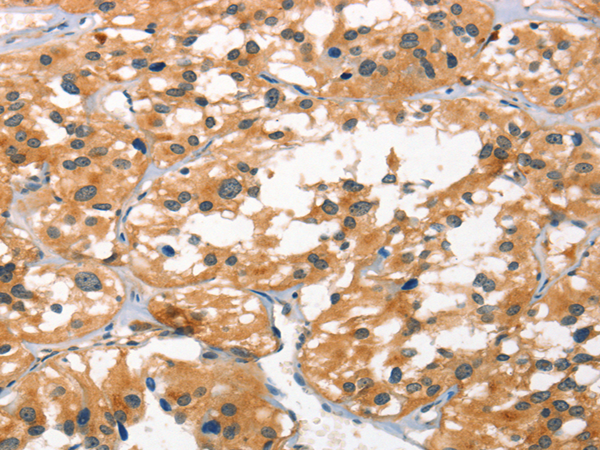

分类: 科研抗体货号: P04769别名: CD318; TRASK; SIMA135应用: WB,IHC反应种属: Human